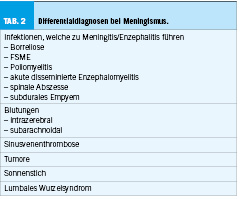

Die Symptome lassen primär an eine Meningitis respektive Enzephalitis denken, wobei ein Spannungskopfschmerz bei zusätzlicher Infektion im Magen-Darm-Bereich als Ursache der Beschwerden nicht auszuschliessen ist. Weiter könnte man an eine (septische) Sinusvenenthrombose denken (Tabelle 2).